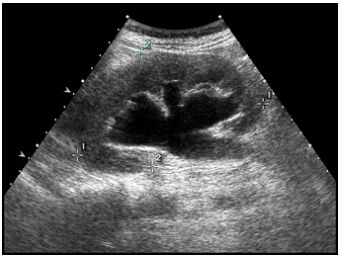

22.患者接受大腸鋇劑灌腸(barium enema)攝影的結果如下圖,最可能是下列何種疾病?(A)腸套疊 (B)惡性腫瘤 (C)腸扭轉 (D)腸炎